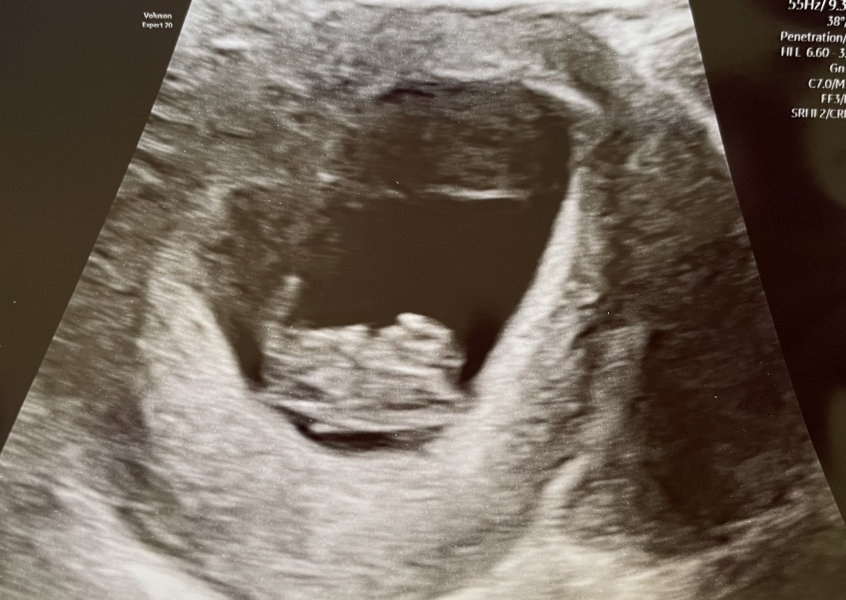

I got a picture at my 8+5 scan, but it's making me a bit anxious as it looks nothing like I thought it should. I expected at least a visible outline, but it looks very odd šŸ˜•

@KittyFantastica If it helps this was my 8 week scan with DD. Total blob šŸ¤·šŸ»ā€ā™€ļø